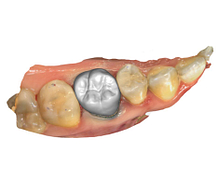

Crowns and Bridges

Inlays and Onlays

Digital technologies allow for extremely precise measurements and fabrication of dental restorations. This precision leads to a better fit, which can improve the longevity of the restoration and the overall health of the surrounding teeth and gums.

With advanced software, dentists can create restorations that closely match the color, shape, and size of a patient’s natural teeth. This results in a more natural and aesthetically pleasing appearance.